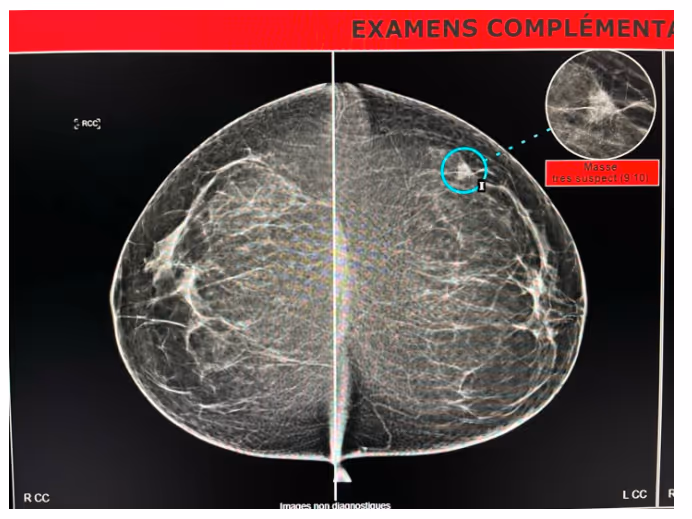

- MammoScreen® AI points to an increased lesion in opacity in the left breast’s upper outer quadrant. This localized image confirms a speculated mass of the left breast.